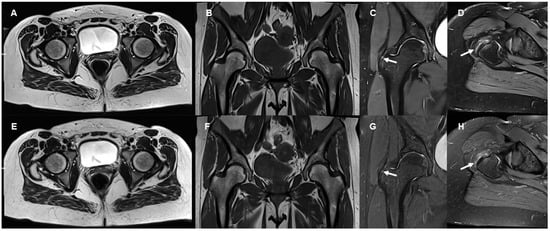

3.1. Image Quality

3.2. Delineation of Anatomic Structures and Internal Derangement